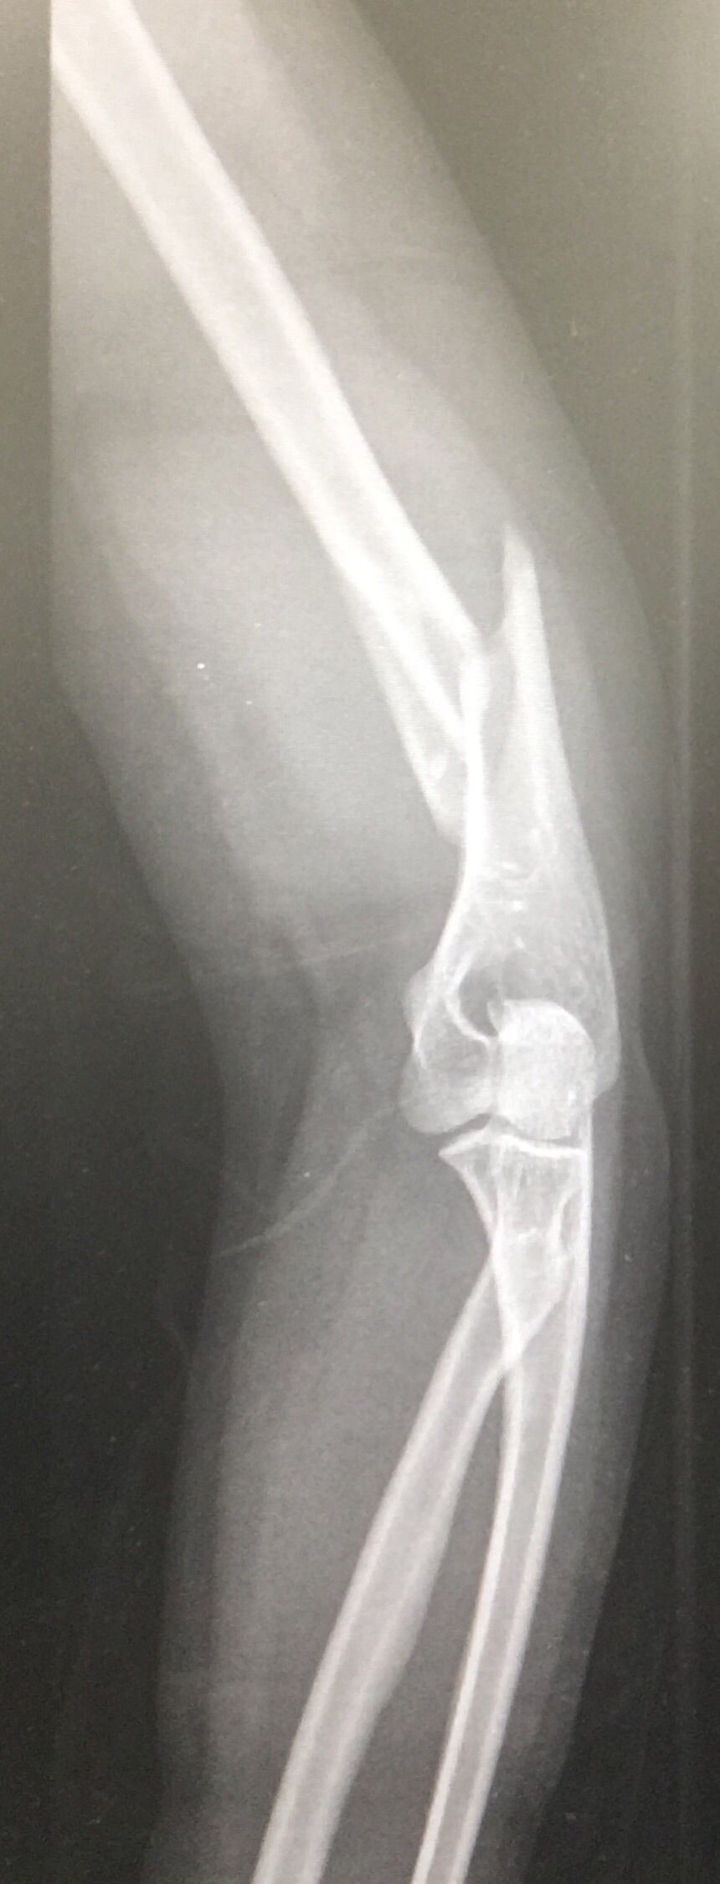

RTA patient

Distal humerus fracture

Distal end of humerus fracture